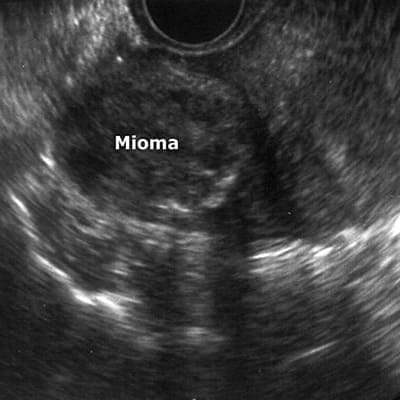

Miomas uterinos